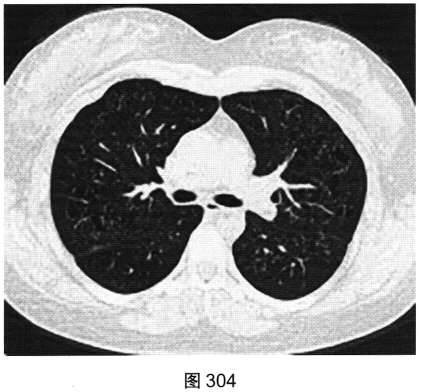

- [材料题] 患者女性,32岁,因“间断刺激性干咳1年,发现肺部囊性病变8个月”就诊。患者无发热、咯血、胸痛、呼吸困难。服甘草片、阿莫西林无明显好转。胸部HRCT如图302~图307所示。

- 多项选择题2.影像检查所示肺内主要病变的形态、分布特点为( )

A、囊状透亮影形状不规则、大小不一

C、囊状透亮影形状规则,大小及肺内分布均匀

G、囊壁较薄、略欠均匀,部分囊壁欠连续

- 多项选择题4.[提示]患者有长期吸烟史,已戒烟1年; 血ESR、CRP(一),血嗜酸性粒细胞(一), 血免疫球蛋白、免疫固定电泳及VEGF-D(一),ANA、ANCA(一); 抗dsDNA(一);腹部超声未见明显异常; 肺通气功能正常。给予拜复乐抗感染、沐舒坦化痰等对症治疗,咳嗽症状略缓解。结合患者临床及CT表现, 首先考虑诊断为( )

B、肺朗格罕细胞组织细胞增生症